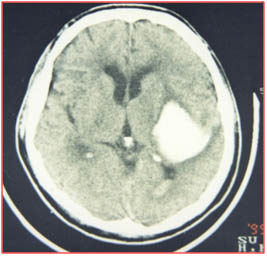

高血壓腦出血的外科治療 外科治療適應(yīng)項目: 1.清除血腫,解除對周圍腦組織的壓迫; 2.降低顱內(nèi)壓(ICP),改善腦血流; 3.解除急性梗阻性腦水腫; 4.解除和防止腦疝。 手術(shù)早期清除血腫能降低血液和血漿產(chǎn)物的毒性作...

高血壓腦出血的外科治療 外科治療 適應(yīng)項目: 1.清除血腫,解除對周圍腦組織的壓迫; 2.降低顱內(nèi)壓(ICP),改善腦血流; 3.解除急性梗阻性腦水腫; 4.解除和防止腦疝。 手術(shù)早期清除血腫能降低血液和血漿產(chǎn)物的毒性作...